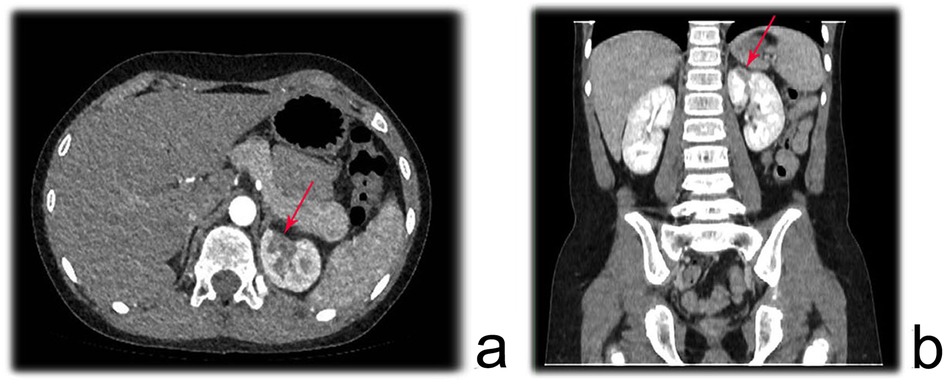

Prior to the examination, the child was required to fast for 4–6 h to reduce the likelihood of adverse reactions to the contrast agent. For children who were uncooperative, oral administration of 10% chloral hydrate at a dose of 0.4–0.5 ml/kg was required for sedation. A non-ionic iodinated contrast agent with a concentration of 300 mgI/ml was administered via a 22- to 24-gauge peripheral intravenous catheter placed in the right upper limb or both lower limbs, with an injection rate of 0.07 ml kg−¹ s−¹ (22-gauge <3.0 ml/s, 24-gauge <1.5 ml/s). All children underwent spiral volumetric scanning of the renal artery phase using a CT scanner with more than 128 detector rows, initiated 22–24 s after the start of contrast injection. After scanning, a set of axial images with a resolution of 0.625 × 0.4 mm was used for three-dimensional vascular volume rendering (VR) reconstruction to evaluate the morphology, structure, course, and degree of stenosis of the renal artery. Figure 1 illustrates a region of reduced perfusion in the upper pole of the left kidney on renal CTA.

Figure 1. Renal CTA showing a region of reduced perfusion in the upper pole of the left kidney. (a) axial plane; (b) Coronal plane.